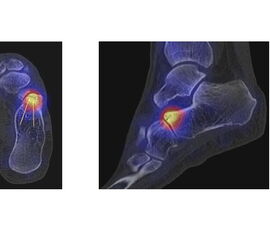

Abbildung 3.2. zeigt ein symptomatisches Os naviculare accessorium Typ II am rechten Fuß.

Zum Lesen der Bildbeschreibung und zur Vollansicht bitte das Bild anklicken. Bild: H. C. Rischke

In Abbildung 3.4. ist ein typisches Beispiel für ein symptomatisches Os trigonum dargestellt.